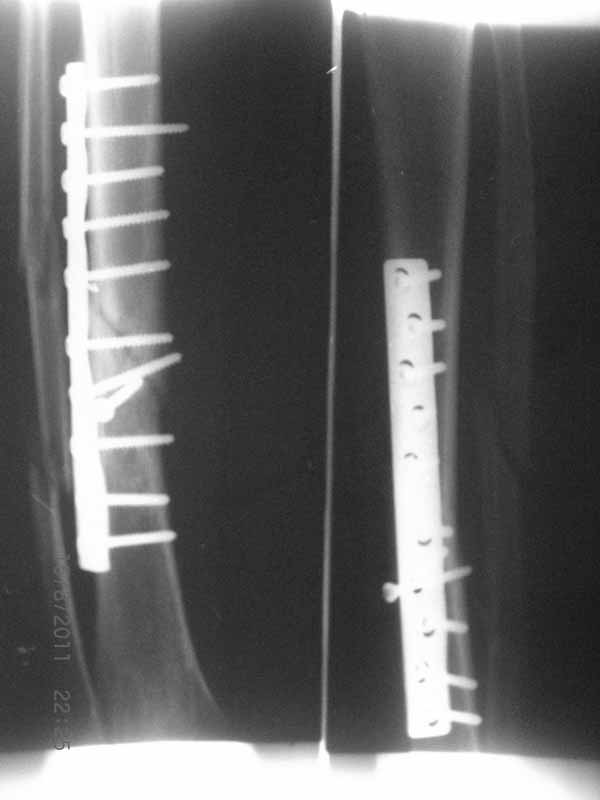

Это гипотрофический ложный сустав. Проблем видится несколько:

1. нарушение трофики в месте перелома.

2. после фиксации в аппарате Илизарова на рентгеногнрамме имеются признаки спицевого остеомиелила. В настоящи момент хотя свищей нет с мая 2011 нет опасно ли фиксировать голень стержнем?

Да уж! Ни один из 3-х оперативных методов предшествующего лечения не был исполнен правильно. Везде был серьезный брак. Хотя любой из методов вполне мог бы и должен был бы привести к сращению,...если бы, да кабы.. В результате имеем то, что имеем. Что делать? Во-первых - подумать. Во-вторых - еще раз подумать. В третьих - еще больше подумать.

Иван, Вам видится зона перелома мертвой, а мне вовсе нет. Есть ли возможность сделать сцинтиграфию с технецием? Это может доказать нежизнеспособность или воспаление концов. Тогда есть резон для такой "крайней" меры как резекция. Есть ли клинические признаки инфекции в области первичной раны?, п\операционных рубцов?, в местах проведения спиц (нет ли спицевого остеомиелита)?.. В общем, вопросов может быть много.

Если нет данных за инфекцию в зоне перелома мы бы аппараптом дозированно устранили деформацию и, не удаляя дистальный фрагмент сломанного гвоздя, закрыто, после рассверливания заштифтовали бы достаточно толстым и надлежащей длины гвоздем.... Если есть спицевой остеомиелит, то также сначала аппарат, затем рассверливанме и цементный спейсор с а\б согласно посевам, через 2-3 недели удалить спейсор, повторно рассверлить и заштифтовать штифтом, возможно покрытым антибиотиком. А если Вы умело владеете техникой Илизарова, и больной согласен, можете оставить аппарат как окончательный метод фиксации....

На основании каких признаков Вы решили, что кость мертвая! Имеется гиперпластический ложный сустав, как результат недостаточно стабильной фиксации ан предыдущих этапах лечения. В данном случае необходимо решение следующих вопросов:

Примерная ситуация. Пациент 37 лет. Синтезировали где-то пластинкой. Попал к нам через 2 месяца.

19 апреля убрали через проколы пластину с винтами, пересекли fibula, наложили аппарат.

Немного потянули по оси, убрали вальгус, ротацию. 22 апреля (на 3-е сутки) заштифтовали окончательно. 29 апреля выписали из отделения. На все ушло 10 дней.